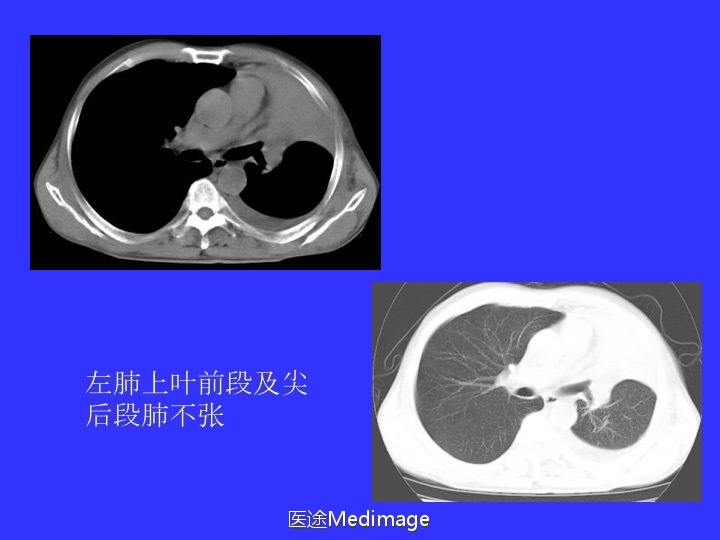

胸部CT阅读与诊断(三)各种肺不张